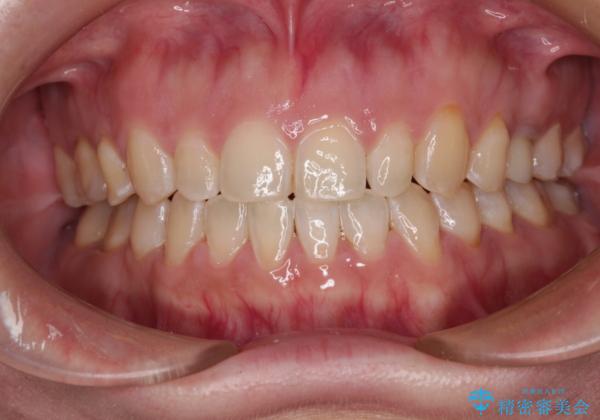

舌の突出癖改善のトレーニングが全くうまくできず、治療期間が長期化しました。

早く治療を終えたいとの要望があり、トレーニング次第と伝えるとようやく練習をするようになり、その後は速やかに上下の隙間が改善されました。